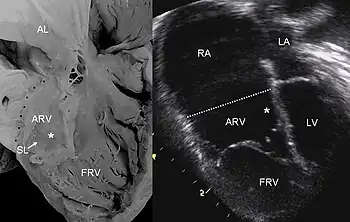

Echocardiogram showing typical findings in severe tricuspid regurgitation

Pathological specimen and ultrasound image of a heart with Ebstein's anomaly

Definitive diagnosis is made by echocardiogram, which is capable of measuring both the presence and the severity of the TR, as well as right ventricular dimensions and systolic pressures.[12] Cardiac MRI or CT scan may also aid in the diagnosis of TR.[3] On imaging studies, a regurgitant volume greater than 45 milliliters or greater than 50% regurgitation across the tricuspid valve is associated with poor outcomes.[3]